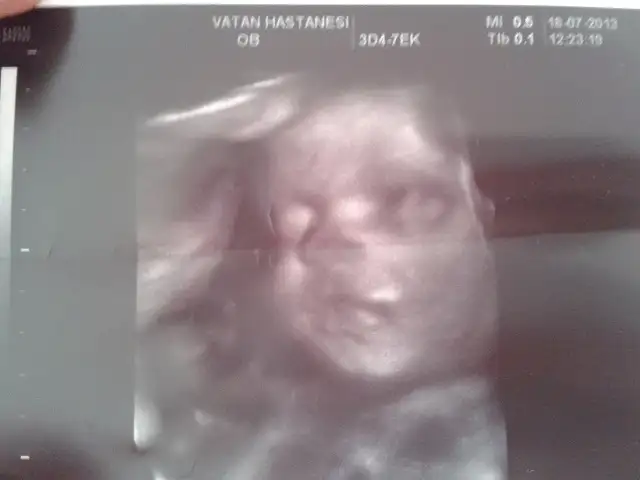

bende kontrolden geldim sat a göre 29+6 yız bugünn, ama BDP miz 33+2 çıktı maşallah gelişimi çok iyi 3-3.5 kilodan aşağı gelmez dedi doktorum,1560 gr olmuş tombişimm, boyunu net söyleyemeyiz ayına göre hesaplarsak 8.aya giriyorsun 35-40 cm arası dedi. FL ye göre 41 oluyoruz. renkli görüyoruz kızımı her gidişimizde elhamdülillahh,annem uyuyordu yine sanırım ama bikaç kez güldü kızımm,ayağı kafasıyla aynı hizadaydı yavrum o nası bi yatmaksa:33:ayy yanaklarııı bi tombikkk annesii ısırsınnn onuu,doktorum bundan sonra hamur işi tarzı şeyleri azalt dedi,bir dahaki kontrolümüz öbür ay, bacaklarım ve çatımda ağrılarım yoğunlaştı dedim,artık ağırlaşıyorsun bu normal dedi,ilaçlara devam iştee,sizinle resmimizi paylaşiim resimlerimizi renkli almıyoruz ama epey belli çıkmış yavrumm,maşallah deyin teyzeleriiiiiiiiiiiii:34::32::nazar:Eki Görüntüle 758738 Eki Görüntüle 758739

Maşallah bebeğine :nazar: Yüzü ne kadar da net çıkmış.. Resimleri bile böyleyse, kim bilir doğunca nasıl da güzel olacaklar :49: